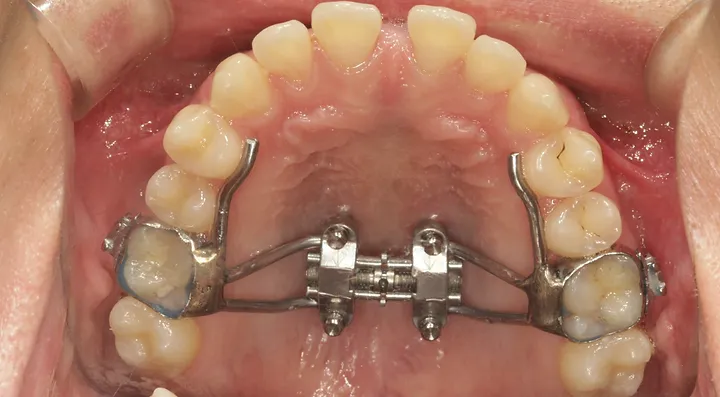

if you have bad transverse maxillary deficiency then definitely look into it. i want to try and get this however i dont know if i'll be eligible seeing as how my lower arch is like 10mm smaller than my maxillary arch.

look how the maxilla was ripped apart on this one holy chit